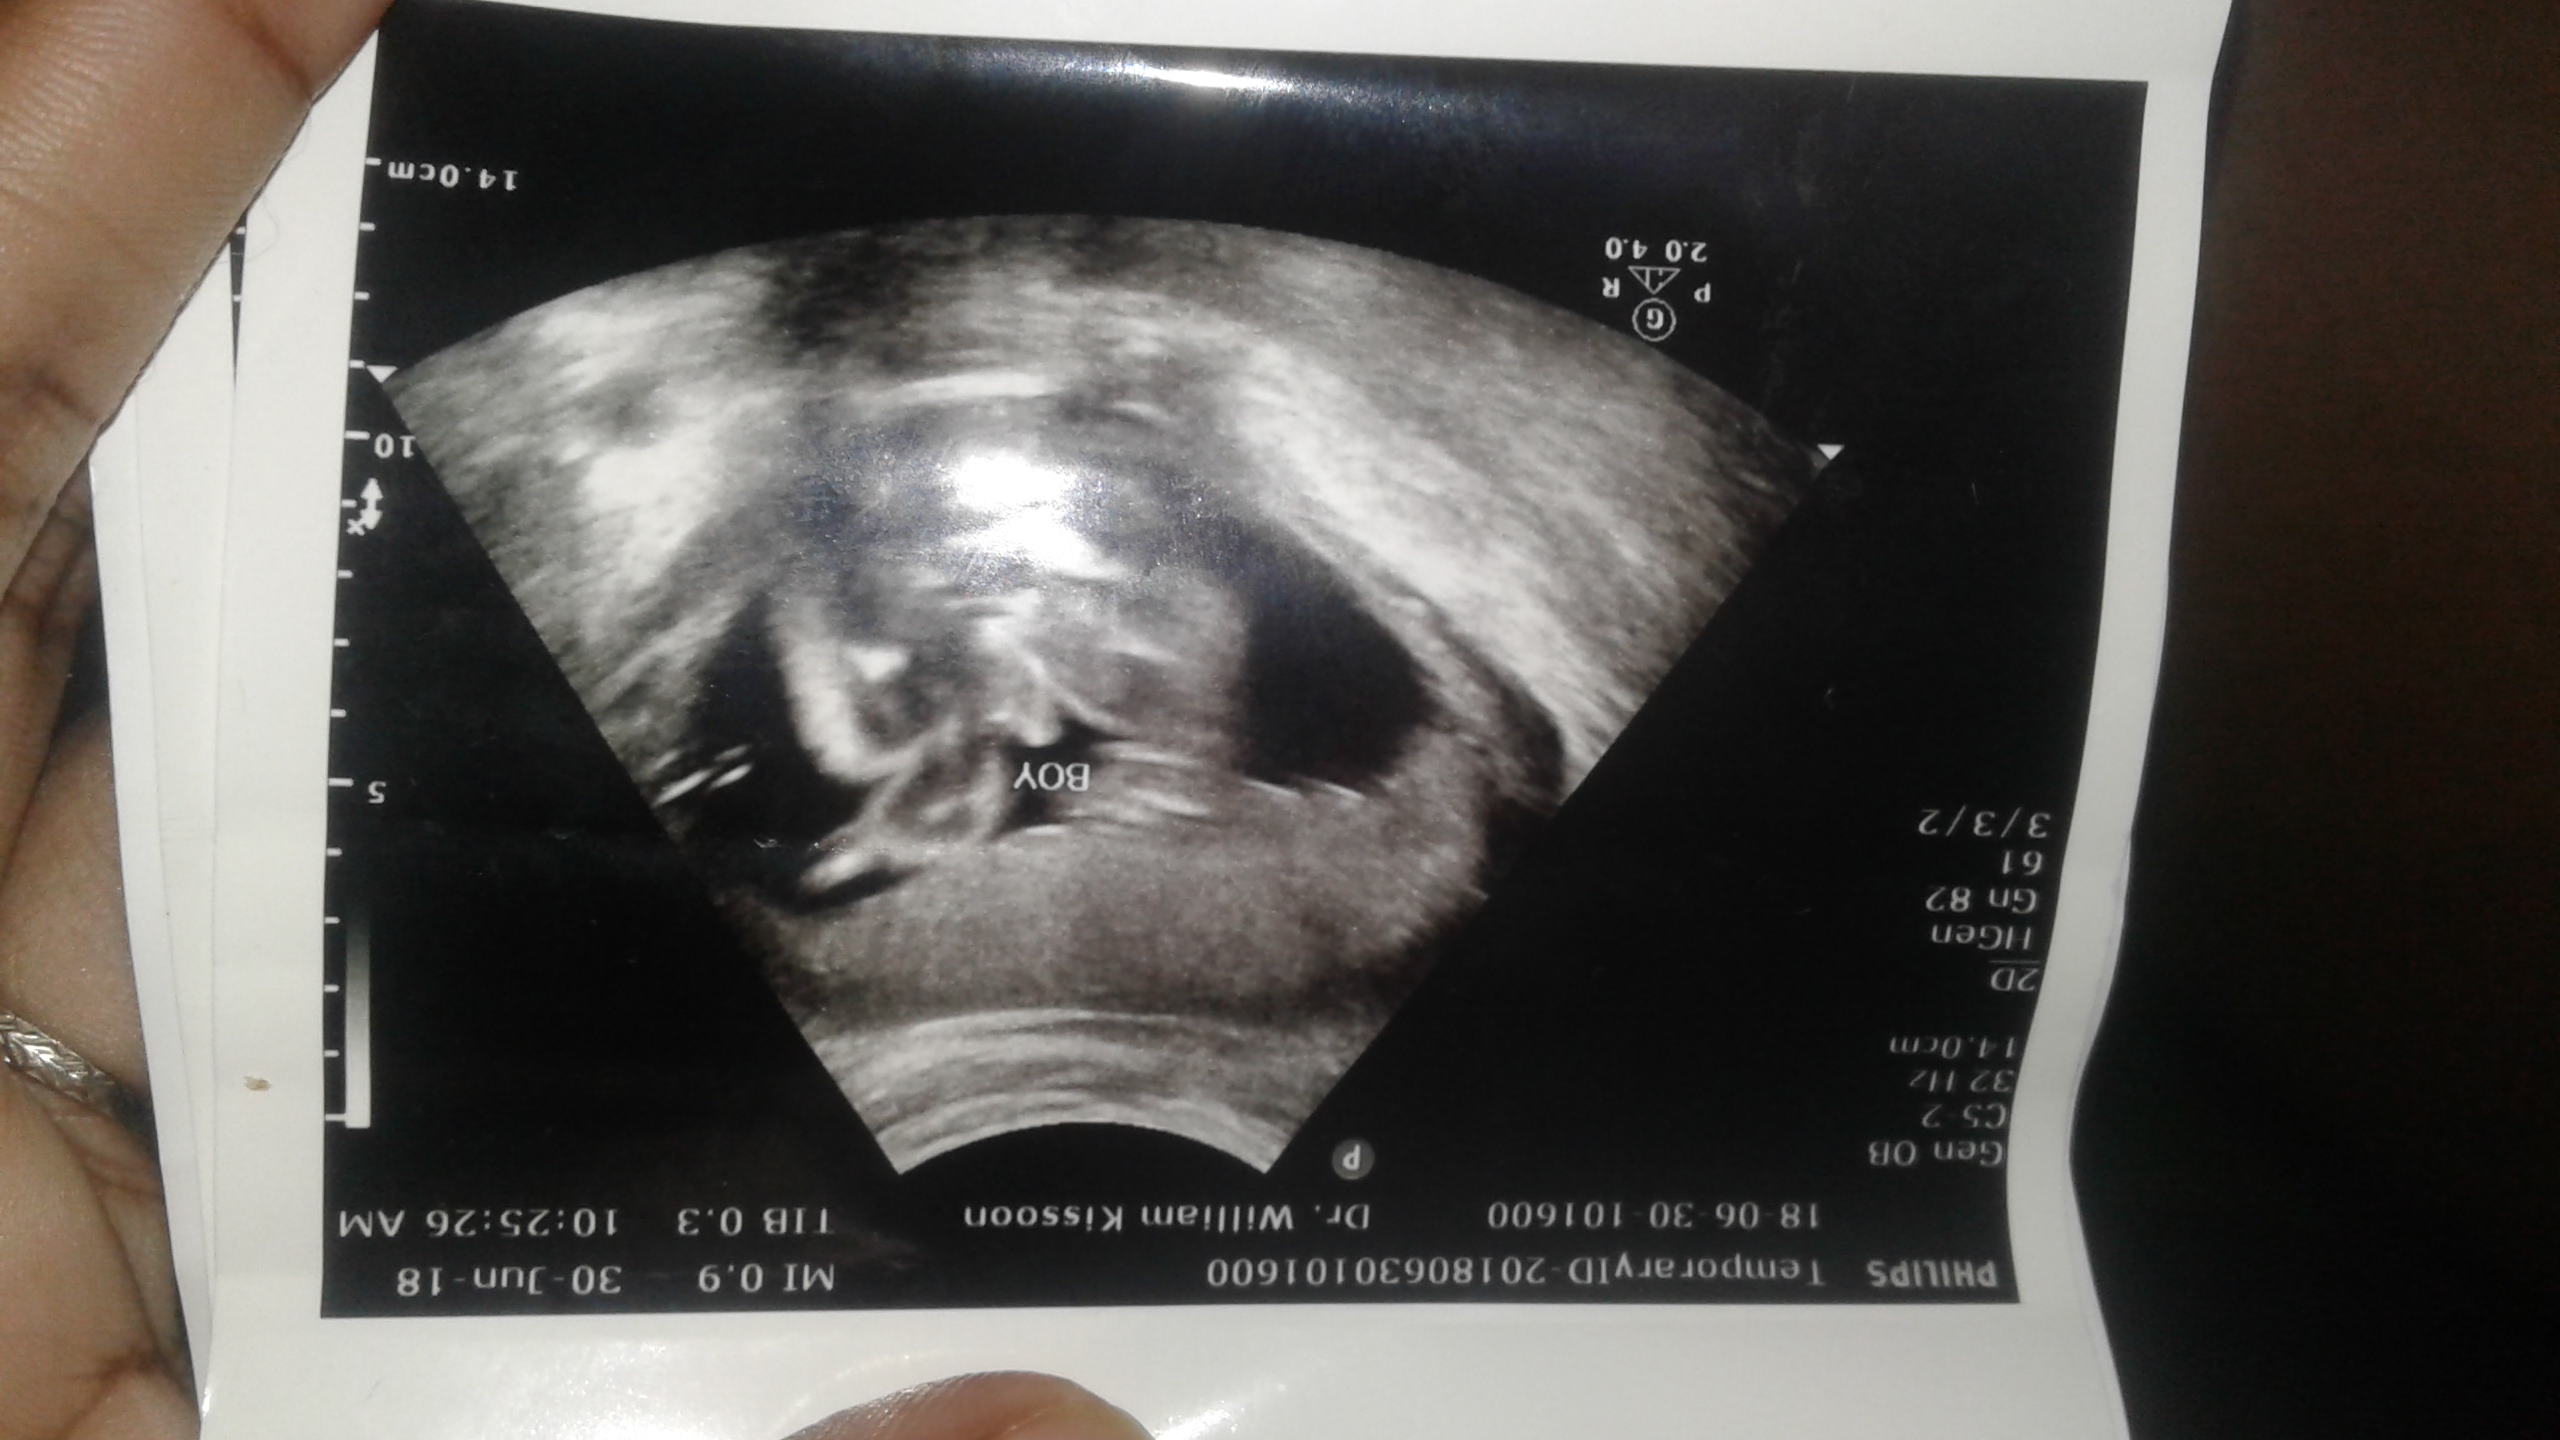

My doctor after a lot of twisted and turning declared boy at my 23 week check-Attachment 39815up. Upon looking at the picture it more looks like baby foot is hiding its private area. Can anyone help me get my bearings in the attached picture.

Not sure what you are hoping for, but congrats on your baby. Definitely looks boy at every angle. Not really sure what part exactly you are confused about, but there is no sign of girl hamburger style mark and a pretty clear penis. Again, congrats :)

I understand why you think that's a foot but the baby would have to be quite a contortionist to get their little foot into that position. I also think boy. Huge congrats!!